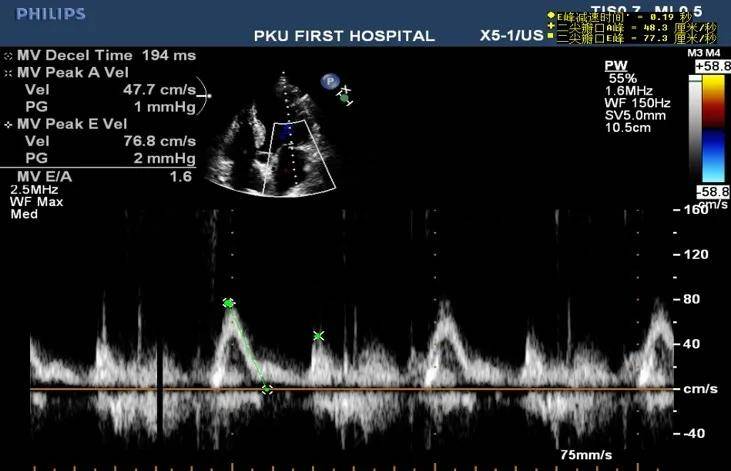

心肌梗死及其并发症的超声诊断

心肌梗塞的超声表现

心脏超声提示广泛前壁心梗

原创华医心诚医生集团专家杨颖:冠心病超声诊断之心梗病例解析